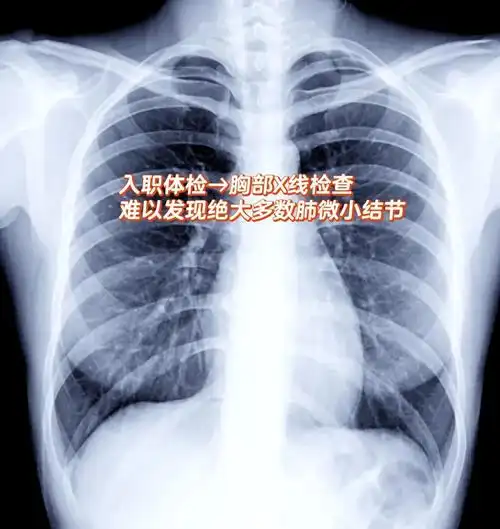

肺结节影响入职?一文解析!